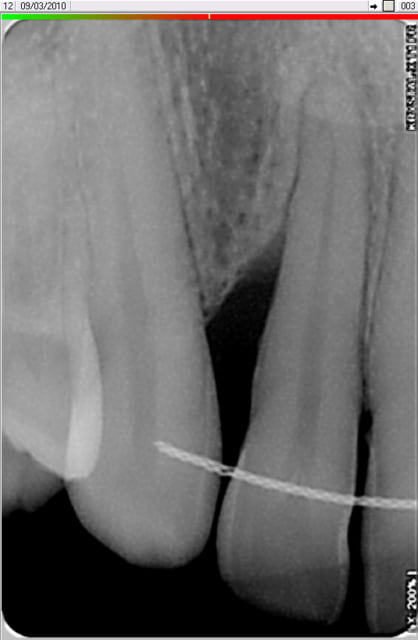

et là? dépuration et surfaçage radiculaire ou endogain en prime?

Dent 12 zllmcw - Eugenol

2010 03 09 002 wpo2gh - Eugenol